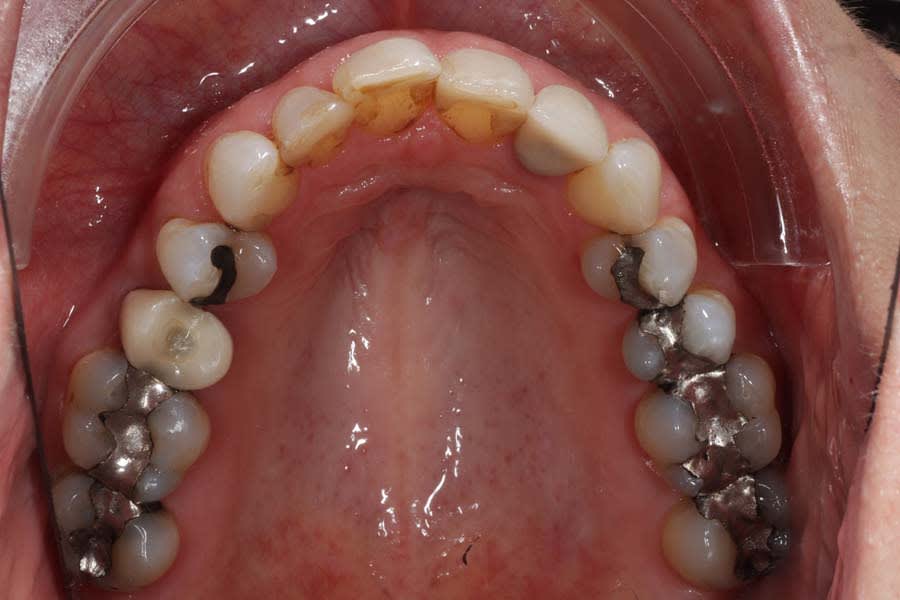

Biomechanical: No active caries or xerostomia was noted, but the fractured amalgam on tooth No. 30 prompted urgent treatment. Large restorations on teeth Nos. 2, 3, 12 through 15, 18 through 20, and 31, along with large Class III composites on teeth Nos. 6 through 9, indicated structural compromises. Root canal treatment on teeth Nos. 4 and 10 (apicoectomy and post-and-core [FlexiPost®, Essential Dental Systems, edsdental.com]) and marginal fractures on teeth Nos. 5 and 12 put these teeth at even further risk. Despite the lack of symptoms, future pulpal pathology was a risk for many of the patient’s structurally compromised teeth (Figure 4 and Figure 5).

Functional: Moderate anterior attrition (1 mm to 1.5 mm) was noted, particularly on teeth Nos. 6 through 9 and 24 through 27, with no significant posterior wear or abfraction lesions. The patient reported slow progression of attrition on her front teeth that had stabilized over the past 5 years, corroborated by a historical photograph. Temporomandibular joint (TMJ) evaluation revealed a 40 mm maximum opening with slight right deviation, asymmetrical lateral movements (8 mm right and 11 mm left), and no pain or joint sounds. She had facial asymmetry as her chin point was 2 mm right of center. CBCT imaging showed a non-reducing anteriorly displaced disc in the right TMJ with osteophyte formation and reduced cortical bone, contrasting a normal left TMJ (Figure 6). Occlusal dysfunction was suspected due to her aberrant chewing pattern, which resulted in unilateral attrition and clenching. Her initial deprogramming identified the first contact on tooth No. 2 with a slide into maximum intercuspation, supporting an occlusal dysfunction diagnosis.